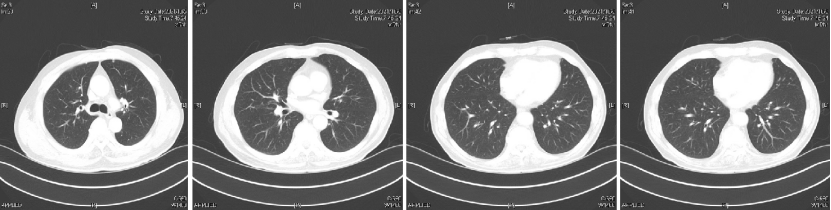

Q1 对于晚期转移性结直肠癌患者,目前,免疫治疗在新辅助治疗中的研究进展和临床应用如何? 结直肠癌是全球第三大肿瘤,转移性结直肠癌的5年生存率只有14%,治疗手段包括手术、化疗、放疗和靶向治疗等。免疫检查点抑制剂的出现也改写诊疗指南。大肠癌dMMR/MSI-H亚型约占所有病例的15%和mCRC病例的5%。由于dMMR/MSI-H的高突变率,肿瘤具有高免疫原性,使其能够激活免疫系统的抗肿瘤作用。 KEYNOTE-177这是一项三期国际开放标签随机对照研究,入选MSI-H/dMMR的IV期结直肠癌患者,比较帕博利珠单抗治疗(200 mg,每3周1次,最多35个周期)与在一线中使用或不使用抗VEGF或抗EGFR单克隆抗体的标准双药化疗,主要终点是PFS和OS。结果显示,帕博利珠单抗组患者的中位PFS时间为16.5个月 VS 8.2个月;3年PFS率分别为42% VS 11%,3年OS率分别为61% VS 50%。帕博利珠单抗组ORR为45.1%(20例完全缓解,49例部分缓解),化疗组为33.1%(6例完全缓解,45例部分缓解);帕博利珠单抗组83.5%的患者至少维持缓解了2年;在化疗组中,只有33.6%的患者缓解持续时间≥2年。KEYNOTE-177研究证实了帕博利珠单抗可以作为MSI-H或dMMR患者的一线标准治疗。 在2021版CSCO结直肠癌诊疗指南中,MSI-H结直肠癌姑息一至三线均推荐免疫治疗,其中帕博利珠单抗作为一线治疗的一级推荐;CheckMate-142研究选择MSI-H/dMMR转移性结直肠癌患者,单免后线vs双免后线vs 双免一线:ORR 39% vs 65% vs 71%,DCR 69% vs 81% vs 84%,一线双免完全缓解率为13%。结果说明双免好于单免,一线好于后线。CheckMate-142研究具有划时代意义,它将免疫治疗从后线前移到一线。 COMMIT研究是一项前瞻随机开放标签的三期临床研究,评估了阿特珠单抗单药治疗对比mFOLFOX6(氟尿嘧啶、奥沙利铂、亚叶酸钙)+贝伐珠单抗+阿特珠单抗一线治疗dMMR或MSI-H转移性结直肠癌的疗效和安全性,目前该试验还在进行中。未来该项研究的结果将回答对于MSI-H晚期结直肠癌,在一线免疫治疗的基础上联合化疗和抗血管靶向药物是否可以进一步提高免疫治疗的疗效。 CheckMate 8HW是另一项随机对照三期临床研究,在一线治疗dMMR或MSI-H转移性结直肠癌中,比较纳武利尤单抗单药、纳武利尤单抗联合伊匹木单抗以及研究者选择的化疗这3种方案的疗效。这项研究将头对头地比较对于MSI-H晚期结直肠癌双免联合是否优于单免的疗效。 Q2 对于MSI-H/dMMR型局部晚期结直肠癌(LACRC),新辅助免疫治疗探索的进展与应用前景如何?有哪些潜在预测疗效的生物标志物? 对于MSI-H/dMMR型局部晚期结直肠癌患者,新辅助免疫治疗可以在肿瘤手术前,提前使患者的免疫系统识别肿瘤细胞,从而使患者的免疫系统更好地产生免疫应答。目前结直肠癌新辅助治疗的探索均为二期研究,探索模式多为双免疫或免疫联合化疗方案,直肠癌多为免疫联合放化疗(同步或序贯)的模式。 NICHE研究是探索纳武利尤单抗联合伊匹木单抗用于Ⅰ-Ⅲ期结肠癌新辅助治疗的二期临床研究,研究共纳入40例结肠癌患者,其中21例为dMMR,20例为pMMR(1例患者同时为pMMR和dMMR),81%的dMMR患者和40%的pMMR患者为临床Ⅲ期结肠癌。患者在接受首次免疫治疗后不迟于6周内接受结肠癌手术,dMMR结肠癌缓解率100%,其中完全缓解的患者占60%,MPR为95%;pMMR治疗组27%的患者也对免疫治疗产生了良好的应答。 NICHE2研究,纳入更多患者,探寻非转移性dMMR结直肠癌患者双免治疗(伊匹木单抗+纳武利尤单抗)的疗效,主要终点为安全性,3年无病生存期。结果显示:MPR率95%,PCR率67%,中位随访13.1个月后没有患者出现疾病复发,毒性可耐受。 NCT04165772研究(前瞻性,单臂,Ⅱ期研究),Ⅱ期和Ⅲ期患者接受新辅助dostarlimab(多塔利单抗)共6个月,结果显示CCR率为100%。 PICC研究是特瑞普利单抗联合或不联合塞莱昔布新辅助治疗错配修复蛋白缺陷或微卫星高度不稳定的局部进展期结直肠癌的双臂随机Ⅱ期临床试验,结果显示完全缓解率高达88%,进一步表明dMMR结直肠癌免疫疗效惊人,潜在替代放化疗及手术。 对于MSI-H或dMMR结直肠癌,NCCN结直肠癌指南中,新辅助治疗增加纳武利尤单抗±伊匹木单抗或帕博利珠单抗单药方案;转化治疗可以选择双免疫或单免疫用药方案。 但并非所有患者都能从免疫治疗中获益,故筛选免疫治疗的疗效预测生物标志物将显得尤为重要。近年来研究主要集中在包括MSI-H、PD-L1过表达、TMB-H(TPS3645)、POLE或POLD1基因突变、PI3K/AKT/mTOR通路、新抗原(身份和数量)、免疫系统状态(免疫细胞特征、T细胞受体相关)等。 Q3 您如何看待对于临床中MSI-H/dMMR 转移性结直肠癌患者使用免疫治疗,部分患者仍然会出现耐药问题? Q4 晚期结直肠癌通常预后相对较差、患者生存期不长,依然是我国困扰结直肠肿瘤治疗的瓶颈问题,但有治愈的可能,此时临床医生制定正确合理用药方案尤为重要。今年上半年发布的CACA-RC指南推荐不适合强烈治疗患者应用曲氟尿苷替匹嘧啶片(TAS-102)联合贝伐珠单抗,作为晚期不可切除结直肠癌姑息一线治疗方案。请您谈谈该推荐治疗对我国晚期不可切除结直肠癌患者的临床治疗带来怎样的获益? 今年上半年CACA-RC指南推荐了不适合强烈治疗的患者应用TAS-102联合贝伐珠单抗作为不可切结直肠癌一线治疗方案,是在不可切除晚期结直肠癌一线治疗中石破天惊的一项突破。晚期mCRC的标准化疗方案在指南中是以奥沙利铂或伊立替康为基础的FOLFOX和FOLFIRI方案,在此基础上,可以根据基因分型联合西妥昔单抗或者贝伐珠单抗,但是依旧有部分患者身体状况无法耐受加强化疗,针对这一类患者的治疗方案选择非常有限,且预后情况并不理想。TAS-102+贝伐珠单抗治疗方案毒副反应相对较低,(临床试验提示比贝伐珠单抗联合卡培他滨效果好)疗效确切,在未来较长一段时间内,尤其是目前疫情肆虐,患者不方便住院治疗时,TAS-102可作为国内不适合强烈治疗的mCRC患者及老年患者的一线治疗优选方案,并为患者带来持续的、更优的生存获益。 二 病例分享 专家简介 王峰 教授 医学博士,副主任医师,硕士研究生导师 滨州医学院附属医院肿瘤科副主任 澳大利亚悉尼维斯迈医学中心访问学者 中华医学会放射肿瘤治疗学分会骨与软组织学组委员 中国临床肿瘤学会(CSCO)神经系统肿瘤专家委员会委员 山东省医师协会肿瘤精准医疗医师分会常务委员 山东省医师协会肿瘤放疗医师分会委员 山东省抗癌协会消化道肿瘤分会常务委员 山东省医学会咽喉肿瘤多学科联合委员会委员 山东省医学会烟草病学与戒烟多学科联合委员会委员 山东省健康管理协会消化道肿瘤防治分会常务委员 山东省医学会放射肿瘤学分会青年委员 山东省医学会妇科肿瘤多学科联合委员会委员 滨州市医学会放射肿瘤学专业委员会副主任委员 01 基本情况 (一)基本信息 患者男性,65岁,于2021-08-26第一次入滨州医学院附属医院风湿免疫科。 主诉:发作性右踝关节肿痛3年,再发1月。 查体:双足第一跖趾关节可见红肿,伴局部皮温升高。 既往史、个人史:既往脑梗死病史7年余,未遗留后遗症;有“膀胱结石”病史1年余,未系统诊治;有“痛风性关节炎”3年余,曾于滨州医学院附属医院风湿免疫科治疗。有高血压病史10年余,最高血压180/110mmHg,口服“吲达帕胺片”,血压控制可。 常规检查发现2次大便潜血阳性。 (二)辅助检查结果 1.肠镜检查 直肠、乙状结肠:直肠距肛门7cm可见一巨大溃疡型病变,表面溃烂,污秽苔,周边环堤样隆起,累及管腔1/3周圈,管腔无狭窄,于病变周边多点活检8块,质脆易出血;乙状结肠见一0.5cm*0.3cm息肉,余黏膜光滑,皱襞清晰,蠕动规律;肛管未见异常。降结肠、横结肠:横结肠见一0.3cm*0.4cm 0-IIa型息肉,表面粗糙,余黏膜光滑,血管纹理清晰,未见异常。 诊断:1.直肠Ca(进展期 溃疡型);2.结肠多发息肉——内镜下冷切除术+息肉摘除术。 2.胸部、上腹部未见明显异常。 直肠MR增强+DWI:直肠距肛缘约5.5cm处肠壁明显不均匀增厚,累及长度约6.0cm,呈等/长T1、等/稍长T2信号,T2压脂呈不均匀高信号,DWI呈高信号,ADC图信号减低,增强扫描呈明显不均匀强化,相应局部管腔狭窄,邻近浆膜面模糊,周缘可见小淋巴结。 02 治疗经过 2021-09-08:于全麻下行全直肠系膜切除+末端回肠预防造瘘术。 术中见:肝脏、胃、腹壁等无转移性结节。肿块位于腹膜返折处,活动度差,侵及浆膜。肠周见明显散在肿大淋巴结。 术后病理:直肠下段中分化腺癌,侵犯外膜下脂肪组织,肿瘤出芽分级(高级别,Bd3),侵犯神经侵犯,未见确切脉管内癌栓;两侧手术切缘、环周切缘及标记切缘内均未查见癌累及,肠周淋巴结内未查见转移癌(0/17)。pTNM分期:pT3N0Mx。免疫组化结果:CK(+),MSH2(+),MSH6(+),MLH1(+),PMS2(+),MDR-1(3+),HER2(3+),P53(3+),Ki-67阳性率约70%。 术后诊断: 1.直肠癌II(pT3NOMO)期术后; 2.结肠多发息肉术后; 3.痛风性关节炎; 4.高血压病(3级 很高危); 5.脑梗死。 CSCO指南: 2021-10-04至2022-06-03:FOLFOX方案化疗10周期(奥沙利铂150mg d1+氟尿嘧啶 0.7g d1+4.4g civ);术后预防性放射治疗DT5000cGy/25f,同步卡培他滨。 2021-11-25至2021-12-06:尿培养提示肺炎克雷伯菌感染,结合泌尿外科、感染科会诊意见,给予左氧氟沙星抗感染治疗。 2022-06-12 肺无法穿刺活检。 基因检测示:(直肠)KRAS/BRAF/NRAS/PIK3CA 基因均未检出突变。伊立替康UGT1A1基因检测结果:非风险基因型。 CSCO指南: 2022-06-20:西妥昔单抗联合FOLFIRI方案治疗(西妥昔单抗900mg d1,伊立替康320mg d1,氟尿嘧啶0.7g iv 4.3g civ)。 2022-07-06:骨髓抑制、腹泻,西妥昔单抗联合FOLFIRI方案治疗(西妥昔单抗900mg d1,伊立替康280mg d1,氟尿嘧啶0.7g iv 4.3g civ)。 疗效对比: 循证依据: C-TASK FORCE研究:首个证实TAS-102联合贝伐珠单抗治疗mCRC的疗效及安全性研究。TAS-102联合贝伐珠单抗是难治性mCRC患者潜在治疗选择,更多临床获益有待进一步研究。 TAS-102联合贝伐珠单抗治疗mPFS时间和mOS时间分别为5.6个月和11.2个月。 TAS-102联合贝伐珠单抗不良反应主要为血液学毒性。 日本大样本RWS:TAS-102和瑞戈非尼不同排序的回顾性研究。 日本大样本RWS:TAS-102单药较瑞戈非尼单药,可显著延长mOS,降低AE。 日本大样本RWS:两药序贯疗效优于单药,且≥65岁先用TAS-102获益更显著。 日本大样本RWS:TAS-102序贯瑞戈非尼组持续治疗时间更长。 2022-07-27至今 给予贝伐珠单抗联合TAS-102治疗期间复查CT评估SD,胃肠道反应不重,骨髓抑制Ⅰ度,耐受性尚可。 *本文仅代表专家观点,并经专家审校。